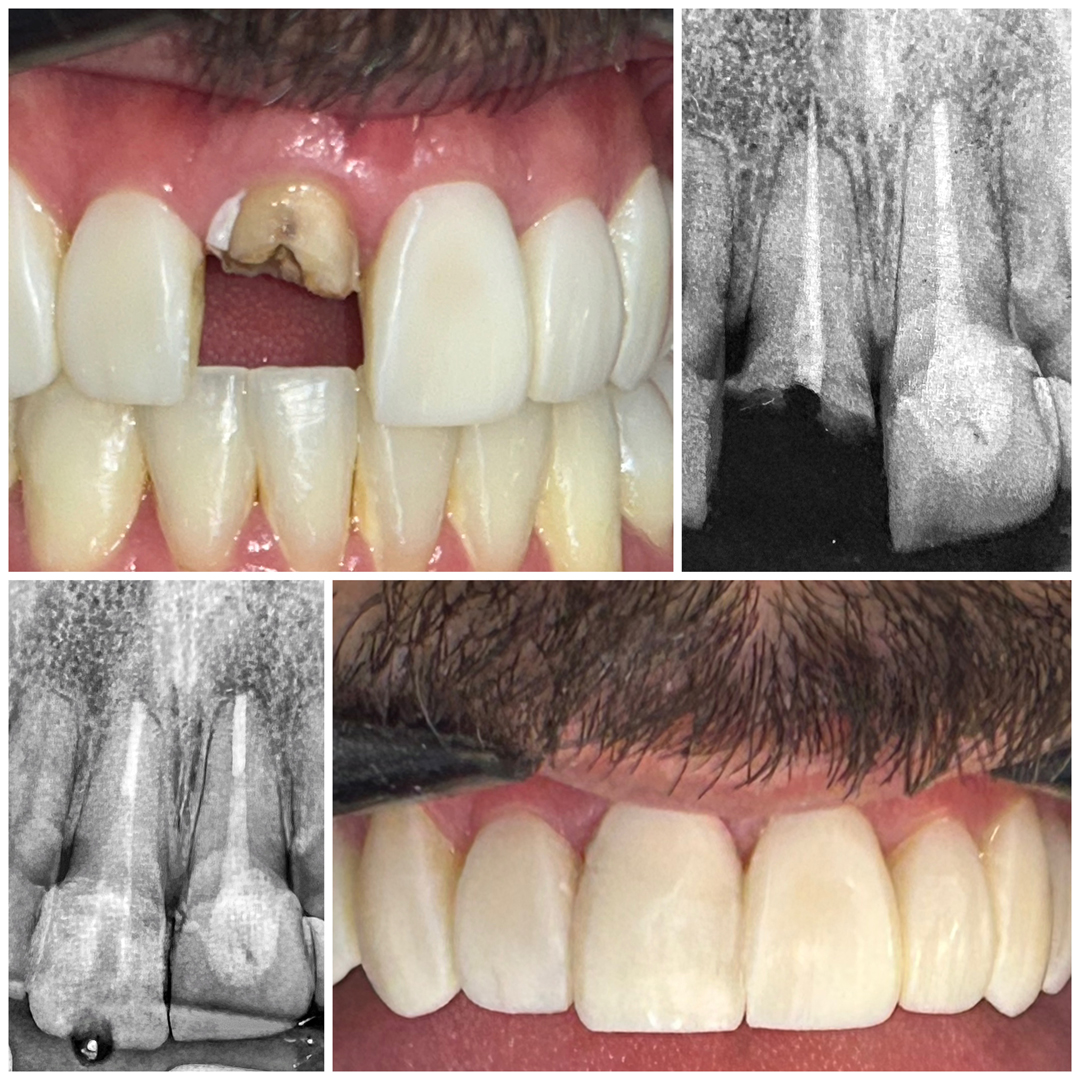

● Tratamento e retratamento de canal

● Confecção de núcleo de fibra de vidro (pino) Se você está sentindo dor, sensibilidade prolongada ou foi diagnosticado com a necessidade de um tratamento de canal, entre em contato.

Seu trabalho é baseado em diagnóstico clínico e radiográfico criterioso, uso de tecnologia e atenção individualizada. Com uma abordagem técnica precisa e humanizada, realiza o tratamento completo, incluindo procedimentos preventivos, tratamento de canal e a reabilitação do dente, permitindo que ele volte à sua função por meio de restauração em resina composta ou coroa em cerâmica e, quando necessário, pino de fibra de vidro, sempre com foco na qualidade de vida e no bem-estar.

● Reabilitação de dentes destruídos